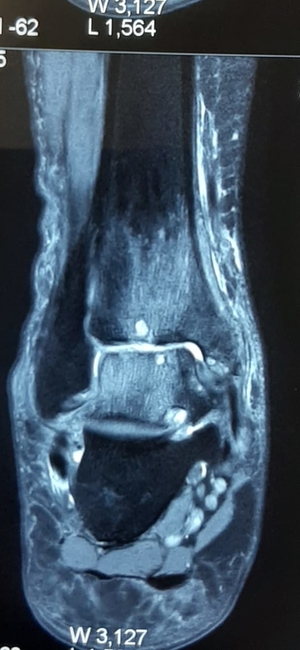

Management of difficult neglected foot and ankle injuries

Presenting an interesting case here:He is 60-year-old active men who met with Road traffic accident 6 months back. He had gross painful swelling in...